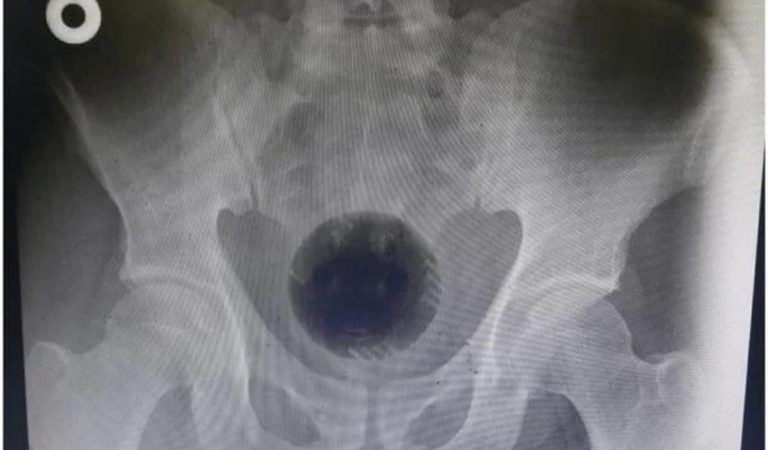

Um homem de 51 anos da Jordânia passou por uma cirurgia de emergência para retirar uma bola de plástico de 7 centímetros de diâmetro, equivalente ao tamanho de uma bola de tênis, que ficou presa no reto. Relatado no International Journal of Surgery Case Reports, o caso foi noticiado pelo jornal The Sun nesta terça-feira (13/9).

A bola, que fazia parte de um aspirador de pó, ficou presa na pélvis do paciente. Ele contou aos médicos que introduziu o objeto no próprio corpo com a esperança de solucionar um problema de hemorroidas. A equipe relatou, entretanto, não ter encontrado evidências desta condição de saúde.